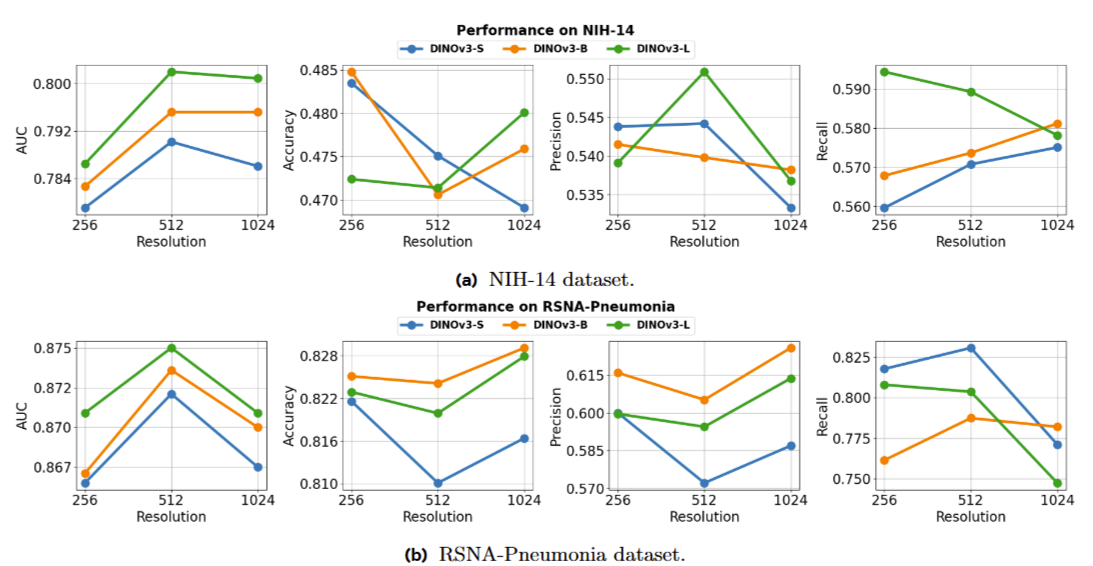

Peiran Wu, Che Liu, Canyu Chen, Jun Li, Cosmin I Bercea, Rossella Arcucci.

[paper]